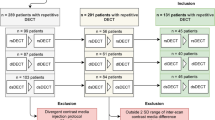

After informed patient consent was waived by the local institutional review board, a structured query to the radiological information system (RIS) was carried out to identify all patients who received ≥ 2 SDCT scans of the abdomen between May 2016 and December 2017. Out of these patients, we identified 79 eligible patients of which 26 underwent biphasic abdominal SDCT thrice and 53 twice. Exclusion criteria were a modified scan protocol in order to reduce contrast media, age ≤ 18 years and renal artery stenosis. The detailed workflow for study inclusion is given in Fig. 1. All patients exhibited a glomerular filtration rate ≥ 30 ml/min. Reasons for examination comprised oncologic staging for melanoma (n = 55), sarcoma (n = 12), lung (n = 8), or GI-tumors (n = 4). Imaging examinations were reviewed for the presence of new ascites or pleural effusion. A significant change in body weight was excluded based on computation of the effective diameter (DE). Anterior-posterior (AP) and lateral (LAT) diameter were determined using an automated script within the Matlab environment (MathWorks) and DE was determined using the formula \( {D}_E=\sqrt{\mathrm{AP}\ x\ \mathrm{LAT}} \) [17].